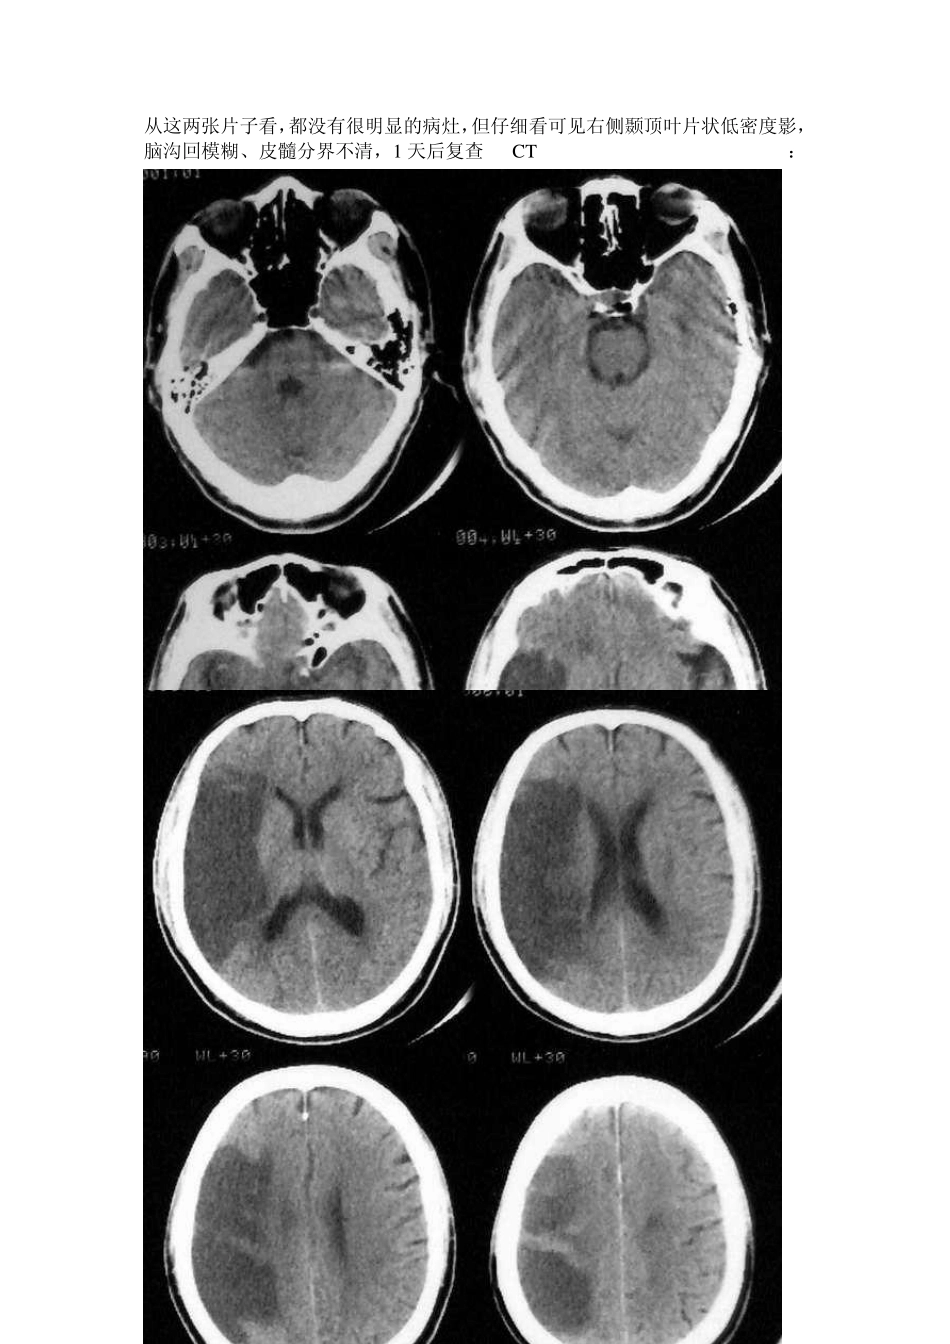

男性,71 岁,左侧肢体无力2 小时,既往健康状况良好。发病后立即查 CT: 从这两张片子看,都没有很明显的病灶,但仔细看可见右侧颞顶叶片状低密度影,脑沟回模糊、皮髓分界不清,1 天后复查 CT: 所谓的超急性脑梗死(临床根据发病时间,目前认为为6H 以内)在病理学上是脑细胞毒性水肿时期。此时,血脑屏障完整。在影像学上要注意有无脑局部肿胀的表现。CT:注意双侧脑沟是否对称,双侧内囊和外囊是否清晰可见,岛叶与外囊是否可以区分。MR:T1W I 上要注意双侧脑沟是否对称,脑回是否有增粗表现。此外还要注意血管是否异常。图 1-2 为超急性期CT 表现。病变在那一边?图 3-4 为MR 的T1W I 和 T2W I,你能看到局部脑肿胀么? 图 1 图 2 图3 图4 图1:左侧外囊与岛叶分界不清。图2:左侧脑沟明显变浅。图3:左侧岛叶盖部的脑回可见增粗;图4:左侧外侧裂内的血管流空影消失。上述表现为超急性期脑梗死的表现。病理基础为细胞毒性水肿。 脑梗塞早期的CT 征象: 1、动脉高密度征(致密动脉征):表现为一段动脉密度增高,CT 值高于正常动脉,而低于动脉粥样硬化斑,其形成机制商不清,主要见于大脑中动脉及其主要分支,其次是椎-基底动脉。 2、岛带征:脑岛灰质、白质界限模糊,呈均一的淡的密度影。 3、豆状核征:豆状核轮廓模糊,密度与脑白质一致或稍低。 4、皮质征:皮质局限性密度减低,与脑白质密度一致。 5、早期低密度改变。 6、占位效应。 以上表现多与脑动脉闭塞后引发的细胞内水肿和血管源性水肿有关,属非特异性表现,其中豆状核征、岛带征、皮质征及早期低密度改变是诊断早期脑梗塞的可*指征,动脉高密度征、占位效应不能单独作为诊断依据。 另外:诊断时需密切结合病史、病征。梗塞灶的CT 表现时间的早晚,除与CT 分辨率和诊断水平有关外,还取决于梗塞灶的大小、部位和缺血程度等。 豆状核征: 左偏瘫1.5 小时,CT 平扫示右侧豆状核密度降低与白质一致 2 天后复查,右侧豆状核区明显低密度影 岛带征: 左偏瘫5 小时,CT 平扫右侧脑岛带区灰质密度降低与白质一致 33 小时后复查,脑岛带区程明显低密度影 皮质征: 偏瘫5 小时,CT示右额颞皮质呈楔形密度减低与白质一致 A 71 岁男性左大脑中动脉梗塞后1.5 小时CT所见。示左岛带消失。(有尾箭头)与正常的右侧岛带对比(三角箭头)。左豆状核似乎正常。 B CT后马上进行左颈动脉造影,示左大脑中动脉M2 段栓子闭塞(有...